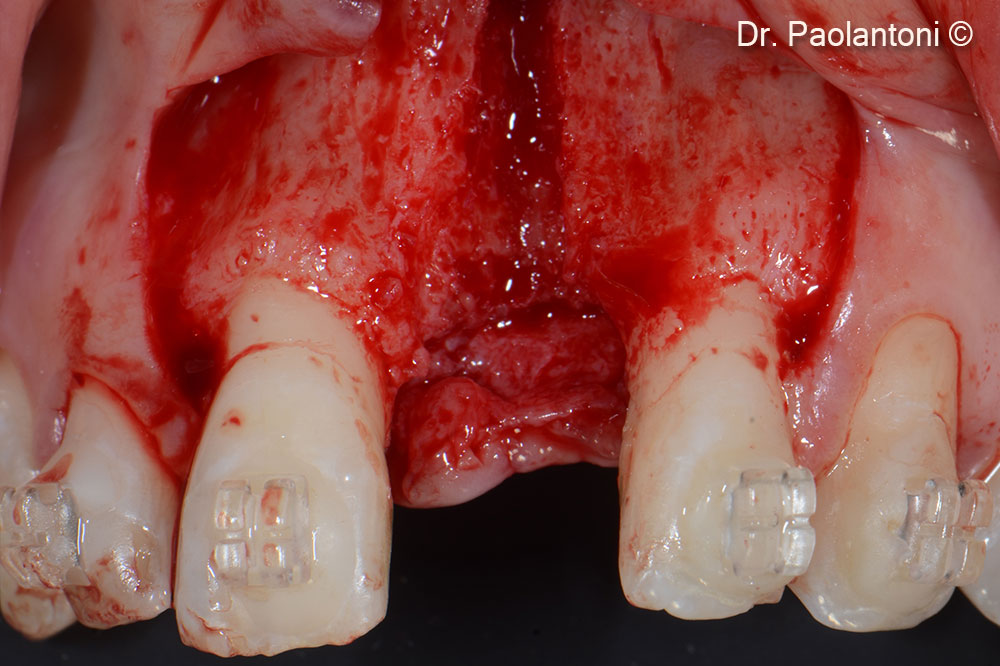

An Evolution collagen membrane is fixed with titanium pins